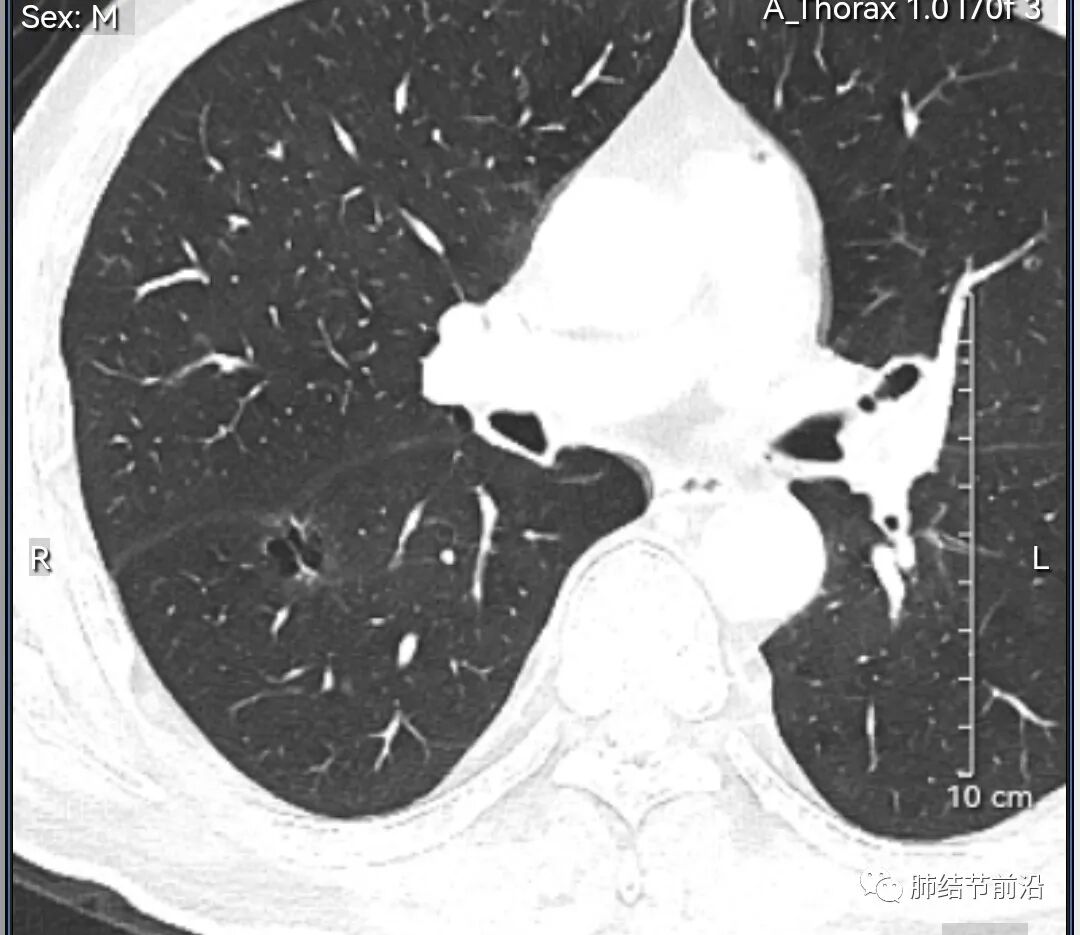

男性,67岁,重度吸烟史。CT发现右下肺囊腔。来看一下这个CT的特点:

该囊腔形态非常有特点,和常见的圆形肺大泡有很大的区别。

1.囊腔中央实性成分,周围有磨玻璃影。

2.囊腔中央有血管。

3.囊腔外周有分叶形态。

4.囊腔有胸膜牵拉。

出现这几种形态,CT可以确认恶性的腺癌。这个囊腔形成的机制,为肿瘤实性成分堵塞细支气管形成活瓣,肺泡内压力增高破裂行成,因此肺内血管成分保留。由于肺泡压力增高,而呈分叶状。另外,也有肿瘤的胸膜牵拉这一特点。

囊腔周围磨玻璃+囊腔中央血管为特征性表现。如果持续存在,几乎可以100%确认为早期肺腺癌。

建议患者手术切除,术后病理为浸润性腺癌,腺泡型,部分为实体型。IA1期,术后不用治疗。